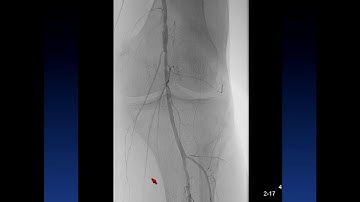

Retrograde Access to Popliteal and CFA